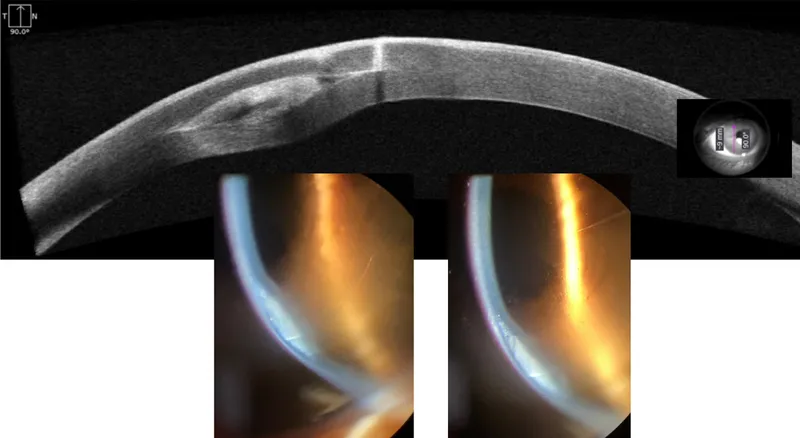

ICRS Implantation - Surgical Symphony

- Femtosecond laser (FS) or manual (diamond knife).

- ~1mm long, 70-80% depth.

- Tunnel Creation:

- FS laser (preferred for precision) or manual dissectors.

- Target depth: ~70-80% stromal thickness.

- Optical Zone (OZ): 5mm, 6mm, or 7mm.

- Segment Insertion: Gentle placement into dissected tunnels via main incision.

- Closure: Suture (e.g., 10-0 nylon) or stromal hydration.